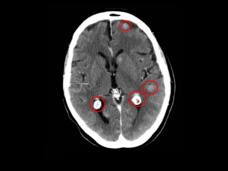

Lorlatinib Slows Growth of ALK-Positive Lung Cancers, May Prevent Brain Metastases

Lorlatinib (Lorbrena) is superior to crizotinib (Xalkori) as an initial treatment for people with ALK-positive advanced non-small cell lung cancer, according to new clinical trial results. Treatment with lorlatinib also helped prevent new brain metastases.